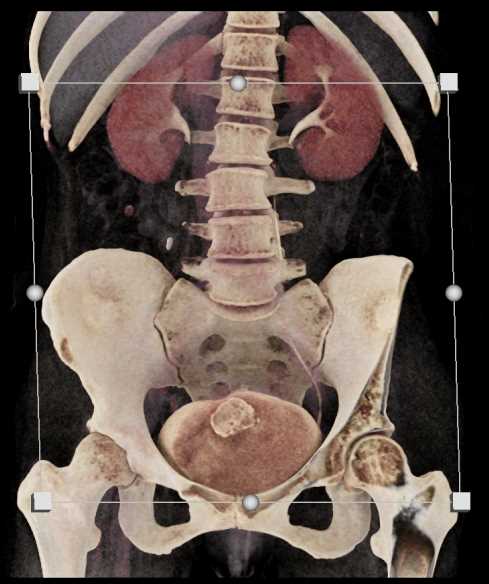

Urachal Carcinoma of the Bladder